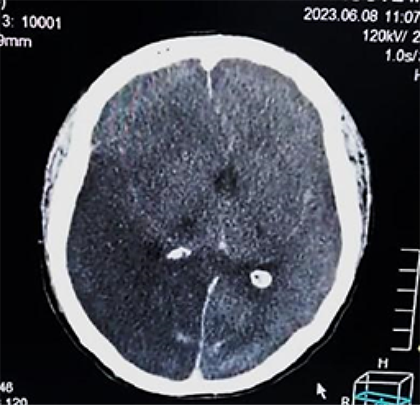

Aun a pesar del tratamiento instaurado de forma multidisciplinaria, permaneció con tendencia a la hipertensión arterial de difícil manejo, bajo analgo-sedación, en asistencia respiratoria mecánica, nuevamente con vasodilatadores endovenosos y medidas de protección cerebral (en primera línea); a las 2 semanas de hospitalización con más deterioro neurológico disminución de los reflejos del tallo cerebral, con tendencia a la bradicardia e hipertensión arterial extrema (probable síndrome de Cushing), se realiza una nueva TAC de cráneo que muestra importante edema cerebral con borramiento de las cisternas peri mesencefálica, compatible con un deterioro rostro caudal (Figura 4a, b)